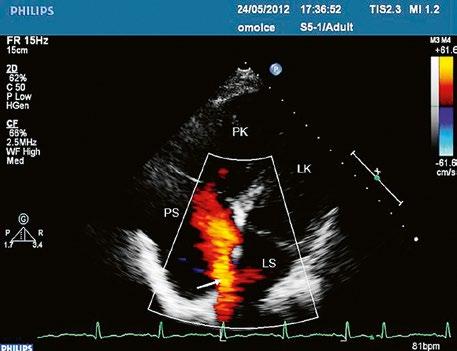

Obr. 45.14 TTE, čtyřdutinová apikální projekce. Kompletní atrioventrikulární septální defekt je označen křížky, představuje komunikaci mezi oběma síněmi i komorami se společnou atrioventrikulární chlopní (AVch)

LK – levá komora, LS – levá síň, PK – pravá komora, PS – pravá síň